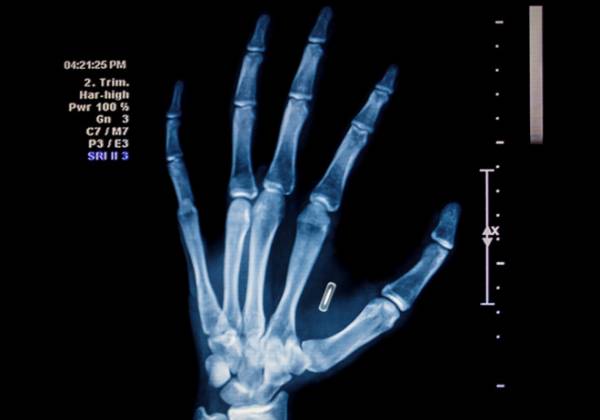

ảnh minh họa

Việc cấy ghép chip cho nhân viên cũng không phải quá mới mẻ. Năm 2017, công ty Three Square Market ở Wiconsin, Mỹ đã cấy ghép chip cho hơn 80 nhân viên. Các chip RFID nhỏ bằng kích cỡ hạt gạo được cấy vào tay để nhận diện, cho phép nhân viên vận hành máy móc đúng trách nhiệm của mình. Thú vị ở chỗ, Three Square bán máy bán hàng tự động nhưng đồng thời cũng là nhà gia công cấy ghép chip.